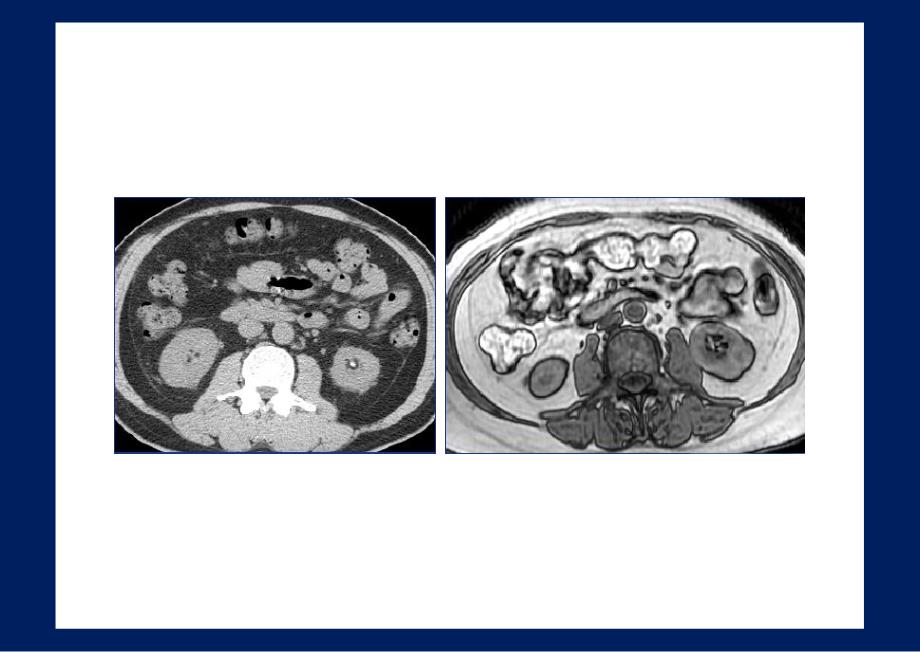

7、化脂肪肉瘤F-49yr,腹膜后高分化脂肪肉瘤T1WICT左肾周间隙去分化脂肪肉3年后瘤3年后脂肪母细胞瘤(Lipoblastoma)起源于胎儿的脂肪组织,多见四肢皮下,腹膜后少见,好发于婴幼儿和年龄较小儿童(3yr,平均12-18m),以脂肪成份为主的软组织团块,可含粘液样物,边界清。T1WI4-Month-old InfantCT脂肪母细胞瘤CorT2WIA 1-yr ChildCT婴儿,腹膜后囊性成熟畸胎瘤T1WICTF-33yr,左侧腹膜后成熟畸胎瘤T1WICTT1WI+CT1WI+CFS-T2WIFS-T2WIT1WIT1WICorT1WI+C脂肪肉瘤与肾血管平滑肌脂肪瘤鉴别 AML肿

8、块与肾实质相连,局部皮质缺损 AML肿块内有较明显血管 同侧或对侧肾有含脂肿块或结节CorT1WI+C右肾AML粘液样脂肪肉瘤好发于大腿、臀部,后腹膜较少,年龄略轻肿瘤以粘液为主,脂肪成份较少,可有间隔和软组织成份CT呈稍不均匀的低密度,似液性,呈假囊性表现。MRI:T1WI呈低信号、T2WI呈高信号,内有少量脂肪信号、间隔或实性成份。增强后呈缓慢进行性强化。M-42yr,左腹膜后粘液样脂肪肉瘤CT+CM-64yr,Myxoid LiposarcomaT2WIT1WI+C1T1WI+C2FS-T2WI左肾周间隙粘液样脂肪肉瘤CT多形性、圆形细胞脂肪肉瘤 不均匀的软组织团块为主,脂肪较少或看不到